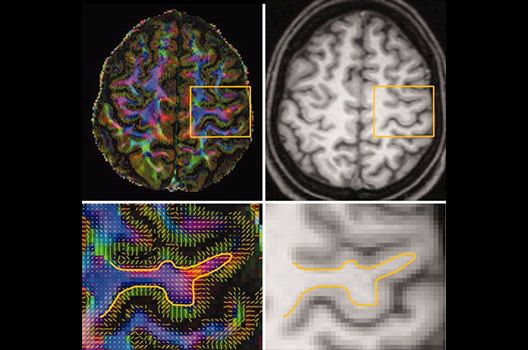

Die Schwerpunkte in der MR-Forschung liegen in der multiparametrischen und funktionellen Bildgebung bei onkologischen und anderen, neuroradiologischen Fragestellungen und umfassen die Anwendung modernster MR-Verfahren sowie die Untersuchung an Hochfeld-Geräten.

Die Magnetresonanztomographie (MRT) ist ein Verfahren, bei dem durch magnetische Kräfte Bilder des Körperinneren angefertigt werden. In der Neuroradiologie können manchmal kleinste Veränderungen schwere Folgen haben; daher forschen wir an der Entwicklung hochauflösender MRT-Sequenzen, mit denen diese Prozesse und auch einzelne Nervenfaserbahnen sichtbar gemacht werden können. Darüber hinaus sind bei vielen Erkrankungen des Gehirns die Blutgefäße betroffen. Daher arbeiten wir an der Neu- und Weiterentwicklung von MRT-Sequenzen zur Darstellung der Blutgefäße und zur Blutflussanalyse (sog. „Angio-MRT“). Einen besonderen Forschungsschwerpunkt unserer Klinik stellen die MR-Protonenspektroskopie und die funktionelle MRT dar, mit denen die Analyse einzelner chemischer Substanzen im Hirngewebe oder die Darstellung ausgewählter Hirnfunktionen möglich ist.